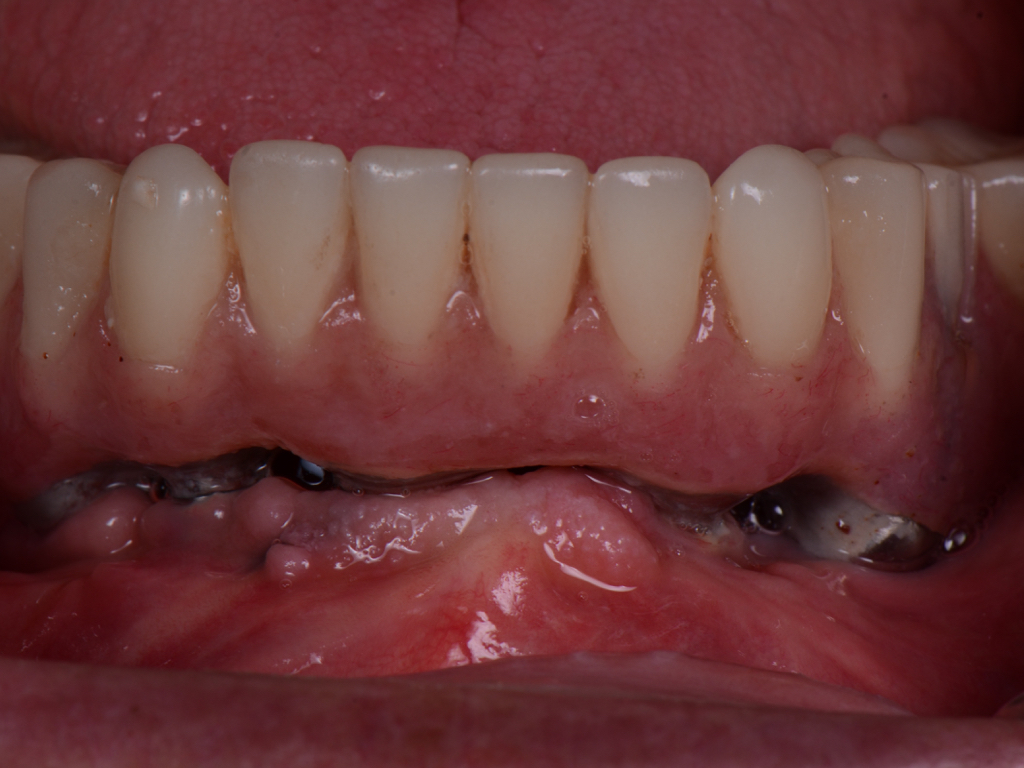

Fig 4. Increased probing depth around an implant with BoP indicates presence of peri-implant disease and the need for taking a radiograph.

Figure 4

Similar to natural teeth, measurements of PPD and BoP before and after treatment are clinical parameters often used to determine the health of dental implants (Figure 4 and Figure 5). However, due to the difference between periodontal and peri-implant anatomy, concerns have been raised about the use of probes in peri-implant tissues around dental implants. These include the risk of peri-implant tissue damage,17,18 risk of damage to the implant surface by the metallic probe,19-21 risk of bacteria inoculation,22-27 and risk of galvanic corrosion resulting from contact between two dissimilar metals.21,28-30 These risks are discussed in the following sections.

Probing is useful to determine the presence of biological complications at the buccal and lingual sites of implants, which cannot be evaluated on a radiograph (Figure 6 through Figure 8). Because of the absence of a periodontal ligament, bone loss on the buccal and lingual aspects of an implant indicates loss of support for the implant and may be a sign of additional circumferential bone loss around the implant.35

Due to the various aforementioned factors that can affect probing depth around an implant, a probing depth of 4 mm to 5 mm around an implant may not be as critical a diagnostic parameter as it would be around natural teeth (Figure 9 and Figure 10). However, probing depth accompanied by BoP becomes a significant concern around an implant. Therefore, while incidental measurement may not be indicative of the health status of the peri-implant tissue, probing at various time intervals enables assessment of health status and disease progression.